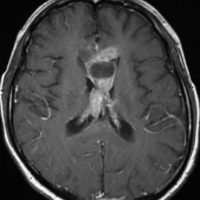

20歳くらいから尿崩症があり,2年後に汎下垂体機能低下症と軽度の認知機能低下を生じました。脳室壁と松果体,神経下垂体にジャーミノーマが広がっているのですが,脊髄背面と脳幹部の周囲にも腫瘍結節が見られました。脳室上衣以外の部位に腫瘍があるので,播種を疑いました。ジャーミノーマの播種というのは実際にはとても珍しくてなかなかみないものです。HCGは軽度の上昇,鼻孔から下垂体部分を生検して病理確定診断して,化学療法と脳脊髄照射 25.2Gy をしました。腫瘍は1コース目の化学療法でほとんど消失したので,他の組織型の悪性混合性胚細胞腫瘍ではないと考えられます。

3年後に脳室壁に再発しました。脳梁と脳弓の機能低下があり認知機能低下は高度でした。松果体と神経下垂体には再発はありません。